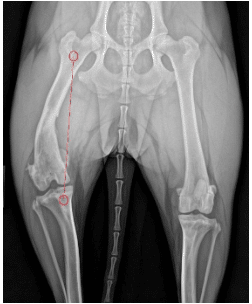

The images to the right (radiograph to the left and a virtual computed tomography (CT) reconstruction from a CT scan on the right) are from the same dog. The radiograph and CT both show how the dog patella is aligned with the quadriceps mechanism. The quadriceps is attached at two points (the small red circles), one at the top of the femur/thigh bone, and one at the tibial tuberosity (front of the shin bone). The quadriceps wants to run a (relatively) straight line between these two points. If the tibial tuberosity is too far to the inside of the tibia, as is the case for the abnormal dog knee above, the line of the quadriceps will be to the inside of the knee. The canine patella falls on that line of the quadriceps, and thus is not centered over the knee (either on the radiograph or the CT).

The images to the right are both from the same dog and both show the patella luxated. The radiograph (X-ray) above left, shows about 14 degrees of femoral varus (ie bowlegged curvature to the femur), which is severe enough to warrant consideration of a femoral straightening. However, that measurement from the dog’s X-ray is inaccurate. The 3D reconstruction from the CT scan, which is a superior way for measuring femoral curvature, shows this patient really only has about 3 degrees of excess curvature and does not need the femur straightened.